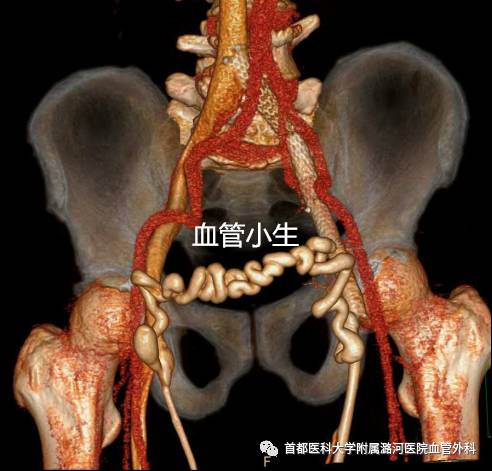

左侧髂总静脉压迫综合征

髂静脉压迫综合征(iliac vein compression svn— drome,IVcS)是右侧髂总动脉与第五腰椎共同压迫 左侧髂总静脉而引起的左下肢静脉回流障碍性疾 病,又称为Cockett综合征或Mav—Thumer综合征。 1957年,Mav和Thumer经组织学研究发现左髂病 变静脉内膜和中层肉皮细胞被结缔组织所取代认 为是左髂总静脉受右髂总动脉和盆腔压迫,动脉搏 动传导引起的静脉壁之问摩擦刺激,内膜慢性增生 和纤维化形成…。1965年,Cockett等通过解剖学、静 脉造影和手术探查的资料进行系统详细的描述,将 该病命名为髂静脉压迫综合征。在此基础上容易 继发左下肢深静脉血栓形成(DVT)。临床表现主要为慢性下肢静脉功能不全,进 行性加重的肿胀、疼痛、浅静脉曲张、色素沉着、溃 疡及深静脉血栓形成等,极大地危害人类类的健康。 近年来,随着介入技术和介入器材的飞速发展,血 管腔内治疗已经成为IVCS治疗的首选。

髂血管解剖特点

左右髂总静脉于第5腰椎体中下部平面右侧汇合成下腔静脉,右侧髂总静脉几乎呈直线与下腔静脉连续,左侧髂总静脉自盆腔横行向右,经腰骶椎前侧,与下腔静脉几乎成直角汇合。腹主动脉相当于4腰椎分出左右髂总动脉,右侧髂总动脉跨越左侧髂总静脉之前方,然后向骨盆右下延伸。左侧髂总静脉在前方受右侧髂总动脉的骑跨,后方受腰骶部生理性前凸的推挤,造成前压后挤。